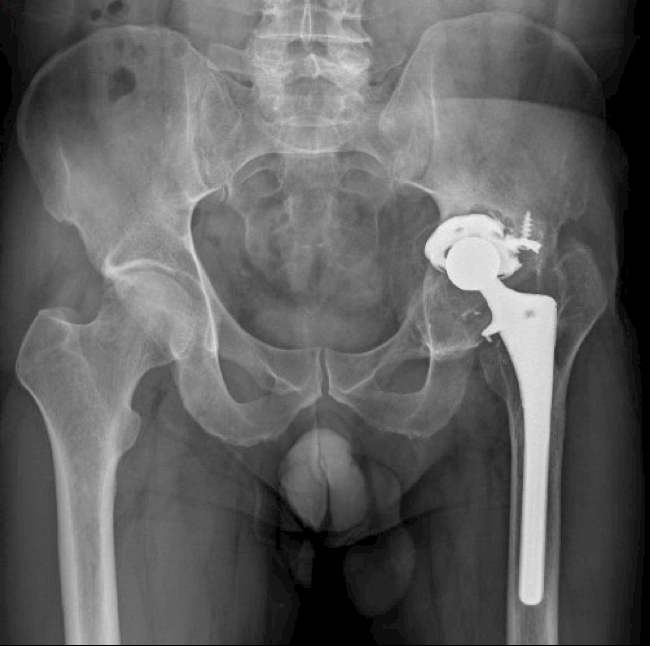

1 month post surgery

6-month follow-up